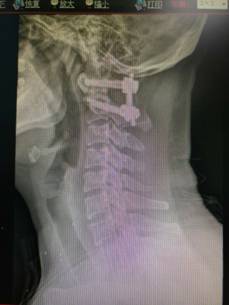

颈椎前路减压融合内固定术治疗脊髓型颈椎病

优点:直接减压,彻底解决突出问题,稳定。

颈椎后开门Arch钛板固定术治疗颈椎后纵韧带骨化症

优点:减压范围广,疗效缺切,保留颈椎的活动度。

寰枢椎固定融合术治疗颅底凹陷、齿状突骨折等

特点:手术风险高。